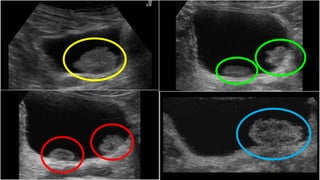

CYSTOSCOPY….. EAU

 The diagnosis of papillary BC ultimately

depends on cystoscopic examination of the

bladder and histological evaluation of the

resected tissue.

 CIS is diagnosed by a combination of

cystoscopy, urine cytology, and histological

evaluation of multiple bladder biopsies.

CYSTOSCOPY….. EAU  Thediagnosis of papillary BC ultimately depends on cystoscopic examination of the bladder and histological evaluation of the resected tissue.  CIS is diagnosed by a combination of cystoscopy, urine cytology, and histological evaluation of multiple bladder biopsies.